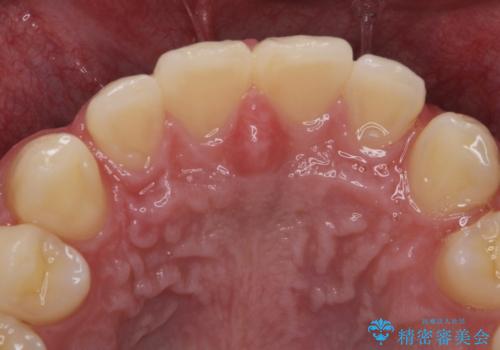

- 歯軋りが気になるとの事で来院。

歯が割れたりするのを予防したいとの事でしたのでナイトガードを作製しました。

ナイトガードを使用することにより歯が割れるリスクが低くなります。